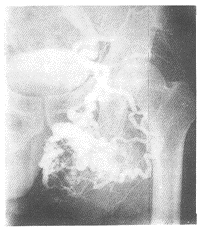

1.2 造影表现:以Seldinger方法经右股动脉插管,先用猪尾巴导管作两侧髂动脉造影,明确肿块系左髂内动脉供血后,再换Cobra导管作左髂内动脉造影,表现为左侧动脉血管包括左髂总、髂内及髂外均明显扩张,以髂内扩张迂曲最明显,动脉早期髂内动脉分支瘤样扩张团状扭曲,后期出现血池样和蚓状曲张血管,血流时间明显加快,可见粗大回流静脉,瘤区血管团最大直径达16 cm(见附图)。诊断为左臀部巨大蔓状血管瘤。

附图 4 s片见髂内动脉明显扩张迂曲及蚓状曲张血管